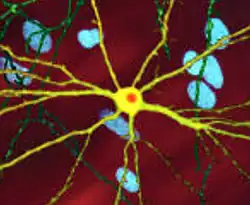

| An edited microscopic image of a medium spiny neuron (yellow) with an inclusion body (orange), which occurs as part of the disease process (image width 360 μm) | |

The toxic action of mHtt may manifest and produce the HD pathology through multiple cellular changes.[52][53] In its mutant (polyglutamine expanded) form, the protein is more prone to cleavage that creates shorter fragments containing the polyglutamine expansion.[52] These protein fragments have a propensity to undergo misfolding and aggregation, yielding fibrillar aggregates in which non-native polyglutamine β-strands from multiple proteins are bonded together by hydrogen bonds.[15] These aggregates share the same fundamental cross-beta amyloid architecture seen in other protein deposition diseases.[54] Over time, the aggregates accumulate to form inclusion bodies within cells, ultimately interfering with neuronal function.[15][52] Inclusion bodies have been found in both the cell nucleus and cytoplasm.[52] Inclusion bodies in cells of the brain are one of the earliest pathological changes, and some experiments have found that they can be toxic for the cell, but other experiments have shown that they may form as part of the body's defense mechanism and help protect cells.[52]

A somatic expansion of CAG repeats is involved in the progression of the disease. Over decades, the HTT gene first sees its CAG repeats expand to about 80 copies: the 35+ CAG locus causes additional slippage errors that expand the repeat. Then the process accelerates, reaching 150 copies within years. There is no significant toxic effect on the cell until 150 copies, at which point a large number of genes become progressively dysregulated. Over months, the medium spiny neuron slowly loses its cell identity until cell death pathways are activated.[57]

Initially, damage to the brain is regionally specific with the dorsal striatum in the subcortical basal ganglia being primarily affected, followed later by cortical involvement in all areas.[58][59] Other areas of the basal ganglia affected include the substantia nigra; cortical involvement includes cortical layers 3, 5, and 6; also evident is involvement of the hippocampus, Purkinje cells in the cerebellum, lateral tuberal nuclei of the hypothalamus and parts of the thalamus.[29] These areas are affected according to their structure and the types of neurons they contain, reducing in size as they lose cells.[29] Striatal medium spiny neurons are the most vulnerable, particularly ones with projections towards the external globus pallidus, with interneurons and spiny cells projecting to the internal globus pallidus being less affected.[29][60] HD also causes an abnormal increase in astrocytes and activation of the brain's immune cells, microglia.[61]